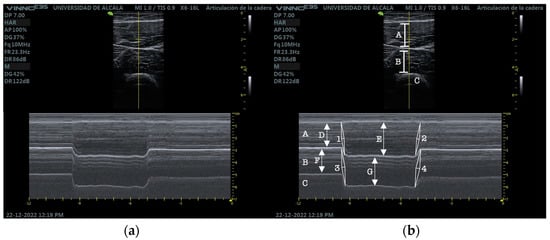

Participants held the contraction for 3 s after which they were asked to relax as fast as possible. Three consecutive measurements were performed with 2 min rest in between to avoid fatigue (Figure 2).

Figure 2.

(a) RUSI M-mode RF and VIM. (b) RUSI M-mode RF and VIM measurements. RF (A), VIM (B), cortical bone of the femur (C), RF at rest (D), RF at isometric contraction (E), RF contraction velocity (1), RF relaxation velocity (2), VIM at rest (F), VIM at isometric contraction (G), VIM contraction velocity (3), VIM relaxation velocity (4).